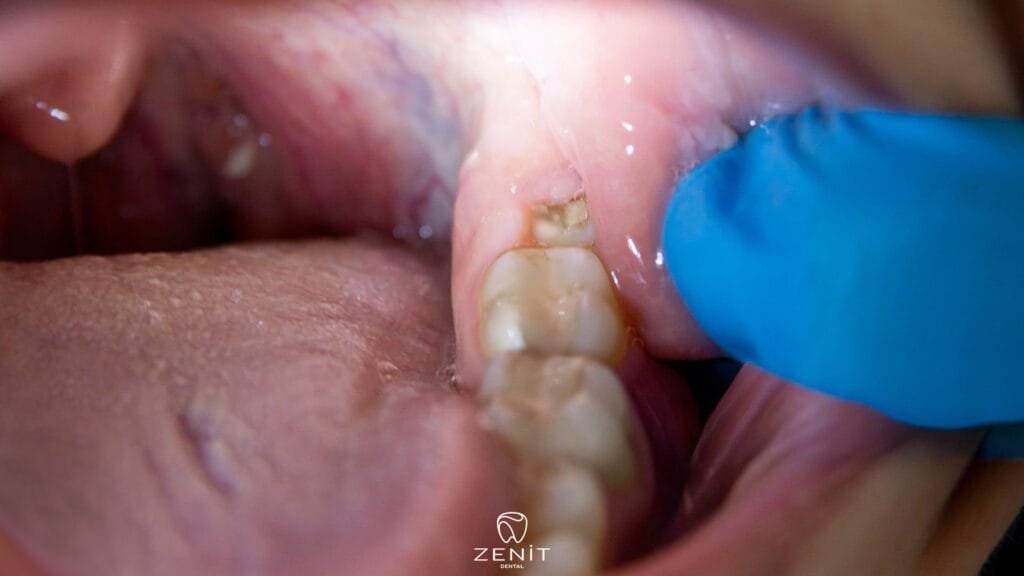

In some people, wisdom teeth emerge smoothly, and because the jaw structure is adequate, no pain or swelling is felt. However, the situation is different for many people. The tooth begins to grow at an angle within the jawbone, or only partially emerges from the gum; this is called a partially impacted tooth. If the tooth never emerges, remaining completely beneath the gum and bone, it is called an impacted tooth.

This condition isn’t just a problem with the tooth itself; it also affects the surrounding teeth. An impacted wisdom tooth can put pressure on the adjacent tooth, causing both jaw pain and misalignment. Furthermore, this compression beneath the gum creates a favorable environment for bacteria to accumulate.

Wisdom tooth pain is usually caused by various factors, such as narrow jaw structure, the direction of tooth emergence, or infection. One of the most common problems is insufficient space in the jaw for these teeth. When the jawbone is small, the wisdom tooth cannot fully emerge and becomes trapped under the gum, pressing on the surrounding tissues, causing a deep, throbbing pain. In some cases, the tooth does not remain completely impacted but rather partially erupts, creating a “pocket” in the gum. When food debris and bacteria fill this space, an inflammation called pericoronitis develops.

The gums become red and swollen, and even opening and closing the mouth can become difficult. Another common cause is a tooth emerging in the wrong direction, meaning at an angle. A sideways tooth can put pressure on the adjacent tooth, causing intense pain felt both in the roots and in the jaw. Although rare, some people can develop cysts around the impacted tooth; these cysts can weaken the jawbone, damage the roots of adjacent teeth, and cause significant discomfort. In short, wisdom tooth pain is a complex process that often affects the balance of not just one tooth but the entire oral cavity.